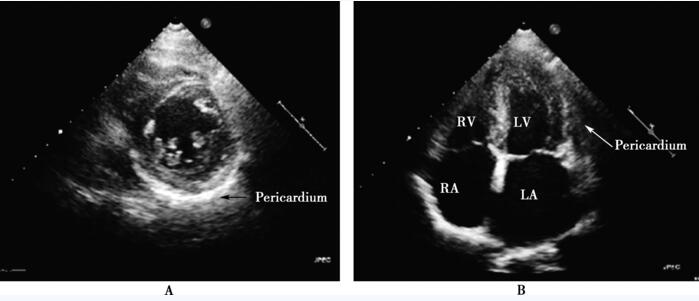

超声心动图虽可显示心包增厚,但缺乏诊断缩窄性心包炎的特异性指标。M型超声心动图可显示增厚的心包组成两条平行线,脏层、壁层心包间清楚间隙至少达1mm,还可见舒张早期心房收缩过程中室间隔突然向后移动;二维超声心动图可显示增厚的心包、室间隔在吸气时膨入左心室、突出的舒张早期充盈以及肝静脉、下腔静脉扩张等。但如果超声心动图医生未能考虑到该病,通常容易忽略上述指征。本例患者超声心动图心尖四腔切面提示双心房扩大、侧壁心包未见明显增厚,左心室短轴乳头肌水平见心包增厚、回声增强(图50-5),但通常考虑心脏外气体干扰致不敢轻易下结论。

图50-5 超声心动图 A:左心室短轴乳头肌水平切面示左心室后壁心包增厚;B:心尖四腔切面示正常心包。Pericardium:心包;LA:左心房;LV:左心室;RA:右心房;RV:右心室